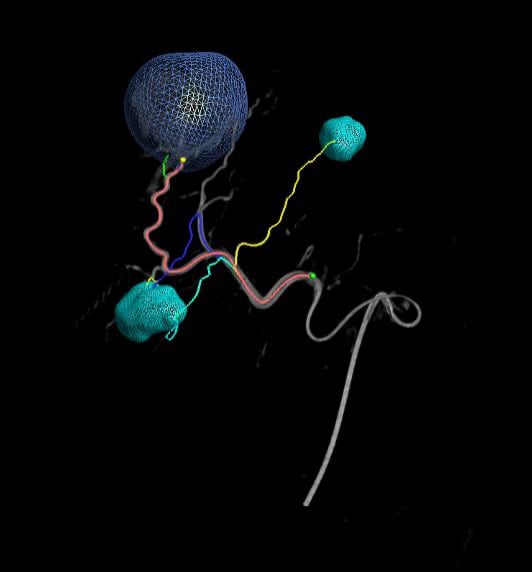

Equipped with sophisticated advanced image-guidance systems and multi-imaging modalities, our physicians may now better visualize and treat patients with complicated diseases. This system includes technology to make this easier in both 2D and 3D with dose reduction technology. It is equipped with integrated Intravascular Ultrasound. Vessel Navigation guidance, 2D Vessel Perfusion, 3D roadmap and Vessel quantitative measurements are offered as well. Vessel Navigator allows reuse of 3D vascular anatomical information from existing CTA and MRA datasets as a 3D roadmap overlay on live X-ray images. With its sophisticated visualization, it provides an intuitive and continuous 3D roadmap to guide you through vasculature during the entire procedure. The system is connected to our PACS system allowing us to visualize previous diagnostic images inside the room.